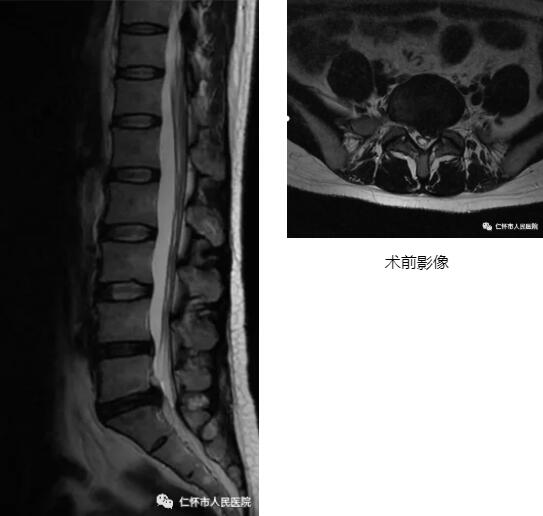

杨女士,30岁,因腰痛了5年多,加有严重的左臀部及左下肢麻木而入院,经我院骨一科主治医师赵兴旺诊断为腰椎间盘突出症,腰椎管狭窄症。由于患者长期左下肢麻木疼痛不适,行走不便,严重影响了患者生活质量,辗转多家医院行相关保守治疗后未见明显好转,有医生建议患者行开放手术治疗,但杨女士考虑开放手术创伤大,因此迟迟未做决定,一直想寻求微创手术治疗,最终就诊于我院。

为尽快缓解患者症状,达到早日康复目标,骨科一病区团队进行了周密的术前讨论和规划,为患者制定了“UBE(单侧双通道脊柱内镜技术)下椎板减压、L5/S1椎间盘髓核摘除、神经根松解”微创治疗方案。在骨科一病区团队的共同努力下,成功完成既定手术方案,在保护神经根和硬膜囊的前提下轻松摘除脱出的椎间盘髓核,避免了传统手术的长切口以及广泛的肌肉剥离,最大限度的减少了手术创伤,病人背部只有两个0.8cm的小切口。患者术前症状消失,可以下床活动,疗效满意。